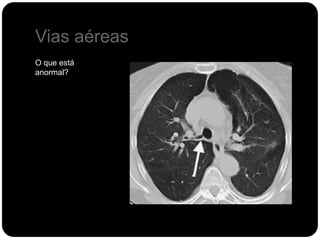

Vias aéreas

O que está

anormal?